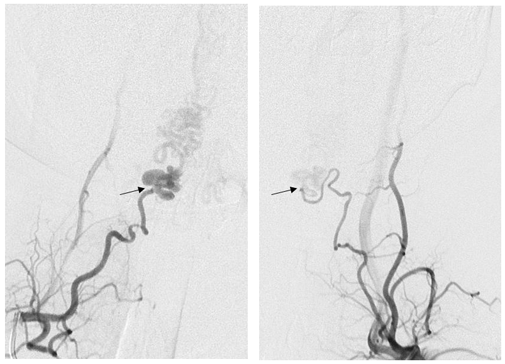

栓塞后复查右侧甲状颈干造影见引流静脉不显影,瘘口完全栓塞。右侧颈升动脉(红箭)经吻合处逆流进入左侧颈升动脉(黑箭)。证实双侧颈升动脉供应相同瘘口。